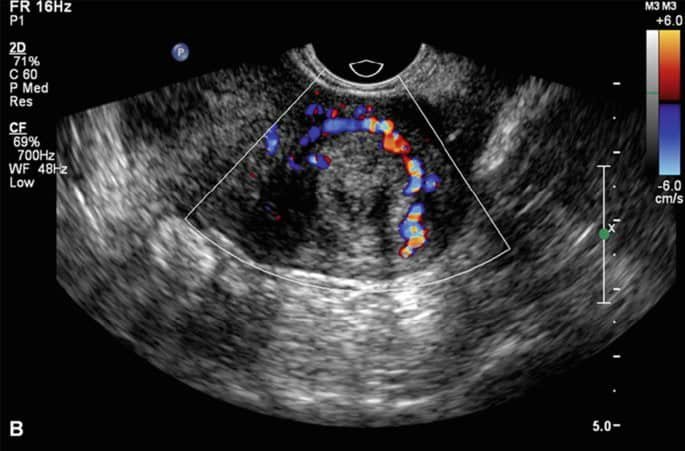

اورام الرحم تظهر في السونار ككتل مستديرة أو بيضاوية، ذات حدود واضحة ومتمايزة عن النسيج الطبيعي للرحم. يمكن أن تكون الألياف كبيرة أو صغيرة جدًا، وتتكون عادةً في جدار الرحم أو تجويف الرحم. في بعض الحالات، يمكن للتليفات أن تمتد إلى خارج الرحم، مما يجعلها أكثر تعقيدًا في التشخيص. كما يُظهر التصوير بالسونار توزيع الألياف الليفية بالرحم ويُساعد على تحديد مدى تأثيرها على بطانة الرحم، وهو أمر بالغ الأهمية إذا كانت المريضة تعاني من مشاكل مثل النزيف الغزير أو صعوبة الحمل.

علامات تليف الرحم بالسونار:

- زيادة سمك جدار الرحم.

- تشوه في تجويف الرحم.

- وجود تكلسات داخل التليف.

- تضخم الرحم أو تغير شكله.

- كتل مستديرة أو غير منتظمة الشكل.

- تغيرات في تدفق الدم باستخدام السونار الملون (Doppler).